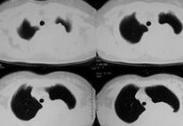

腫瘤性胸腔積液亦稱惡性胸腔積液。大多數(shù)病例可以在胸腔積液中找到惡性細(xì)胞,如果胸腔積液伴縱隔或胸膜表面轉(zhuǎn)移性結(jié)節(jié),無論在胸腔積液中能否找到惡性細(xì)胞,均可以診斷惡性胸腔積液。